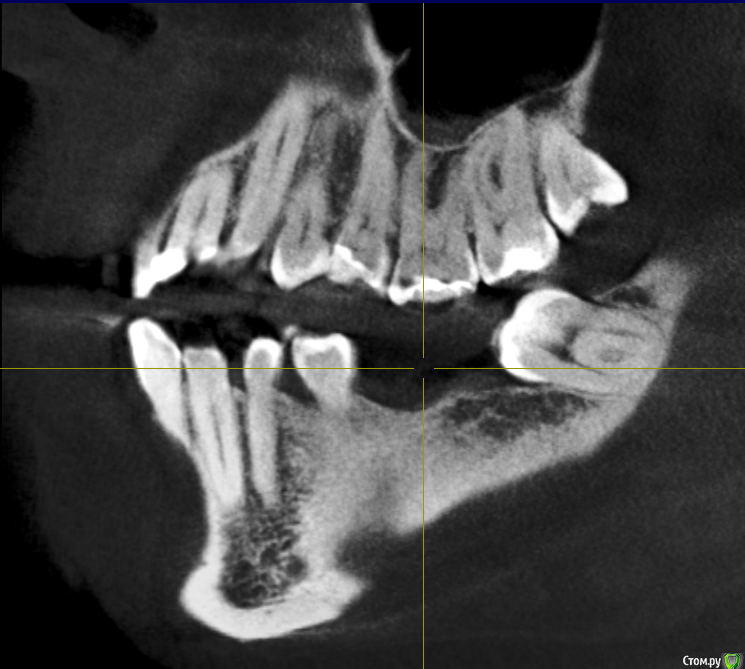

Mariia Опубликовано 9 ноября, 2017 Поделиться Опубликовано 9 ноября, 2017 Уважаемые доктора, добрый день!Посоветуйте, пожалуйста, что можно сделать в моем случае. Давно нет 3-х зубов (более 10 лет), стали стираться 7-ки справа, верхняя 6-ка слева стала опускаться.После нескольких консультаций окончательно запуталась в планах лечения.Понятно, что необходимо устанавливать 3 импланта, но как это сделать? - предлагают ортодонтическое лечение на верхней 6 справа (ставить миниипланты и поднимать) и верхней 7 слева (сдвигать ее, освобождая место для установки импланта, полностью имитирующий нормальный жевательный зуб). - и второе мнение: 7 не сдвигать, поставить вкладку, а 6 спиливать, депульпировать (скорее всего) и ставить керамическую вкладку. 6-ку не поднимать, так как гайморова пазуха находится близко к корню. Собственно, в комплексе с ортодонтией все лечение выходит очень дорогим.Что скажете? КТ по ссылкеhttps://yadi.sk/d/cSYIaF3p3PZFnb Ссылка на комментарий

Bier Опубликовано 10 ноября, 2017 Поделиться Опубликовано 10 ноября, 2017 Посмотрел Вашу КТ.Справа в принципе можно ортодонтией не заниматься, а поставить имплантат в позицию 16зуба, коронка будет чуть меньше стандартной. Проблемы скорее всего не будет. Слева ситуация сложнее. Надо удалить 28,38 зубы, внедрить на миниимплантатах 26з и имплантировать 36,37з Ссылка на комментарий

колесников Опубликовано 10 ноября, 2017 Поделиться Опубликовано 10 ноября, 2017 48,28,38 удалить. Импланты 16,36,37. Пластика десны в области имплантов 36,37. Керамическая вкладка (пломба) на 17,26,27 Ссылка на комментарий

Mariia Опубликовано 12 ноября, 2017 Автор Поделиться Опубликовано 12 ноября, 2017 Добрый день, и еще одно мнение: 7 справа не трогать, поставить вкладку. А в будущем провести ортодонтическое лечение: 7ку или поставить на место 6ки или отодвинуть и освободить место под полноценный имплант (доктор видит риск резорбции и травмы соседних зубов из-за недостатка места, тонкий имплант ставить не рекомендует)А слева предлагает сделать подсадку костной ткани на нижней челюсти - 6 и 7 зубы, чтобы поставить полноценный имплант (тонкий не рекомендует, хотя на прошлых консультациях мне предлагали как раз полноценный и костной ткани хватало). К сожалению, по моей КТ не показали, где идет истончение. Предложил сделать на другом оборудовании и с другим просмотрщиком, чтобы аргументировать свою точку зрения. Соответственно, 8 удаляем. Настолько ли моя КТ не информативна? Нужна ли КТ на операции? Возможен ли такой план лечения? Есть ли какой-то стандартизированный план лечения по моему случаю? Фото выложу чуть позже.Спасибо. Ссылка на комментарий